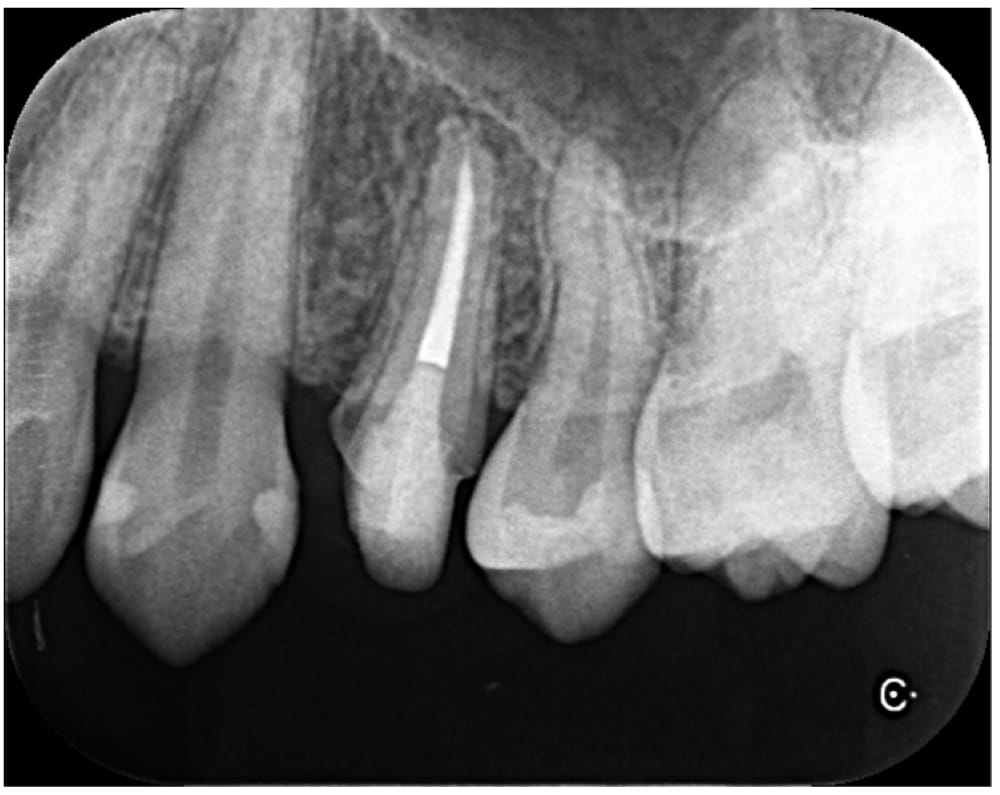

治療後6ヶ月で根尖部の透過像は縮小傾向を認め経過良好のため、ジルコニアクラウンによる最終補綴治療へ移行しました。

術後24ヶ月が経過時点でのCT画像では、もともとはっきりと写っていた根の先の黒い部分は完全に消失し、骨の回復が認められます。被せ物の適合にも問題なく、良好な経過をたどっています。